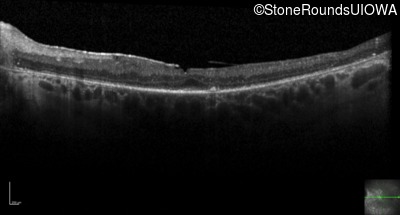

Optical Coherence Tomography - Right - 20/80 +1

Exemplar / OCT Stack

OCT Stack